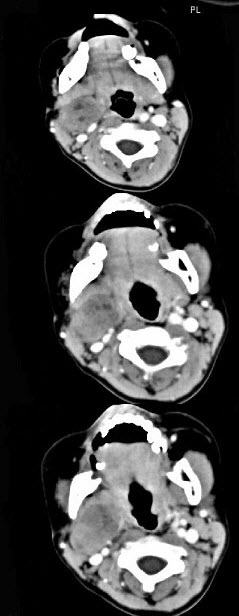

女,4岁,右侧颈部可扪及一包块约两个月,无热无痛,CT如图所示,最可能的诊断为()。

A、咽旁血管外皮瘤

B、咽旁副神经节瘤

C、咽旁脓肿

D、咽旁神经纤维瘤

E、咽旁小唾液腺混合瘤

D